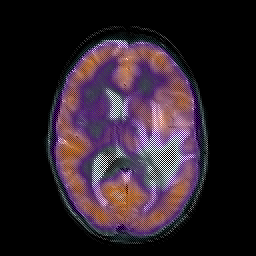

Metastatic bronchogenic carcinoma, overlay -- Slice #12

[Home][Help][Clinical] Slice 12